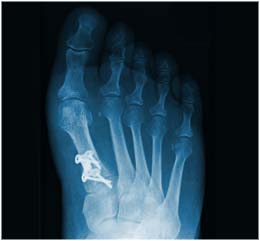

Röntgendiagnostik

Zur präzisen Diagnostik von Verletzungen und Erkrankungen am Skelett ist die Röntgendiagnostik auch heute noch unverzichtbar.

Wir verfügen über eine hochmoderne digitale Röntgenanlage und speziell geschulte Mitarbeiterinnen, die die Röntgenuntersuchung durchführen. Direkt im Anschluss werden die Bilder vom Arzt befundet und Ihnen erklärt.